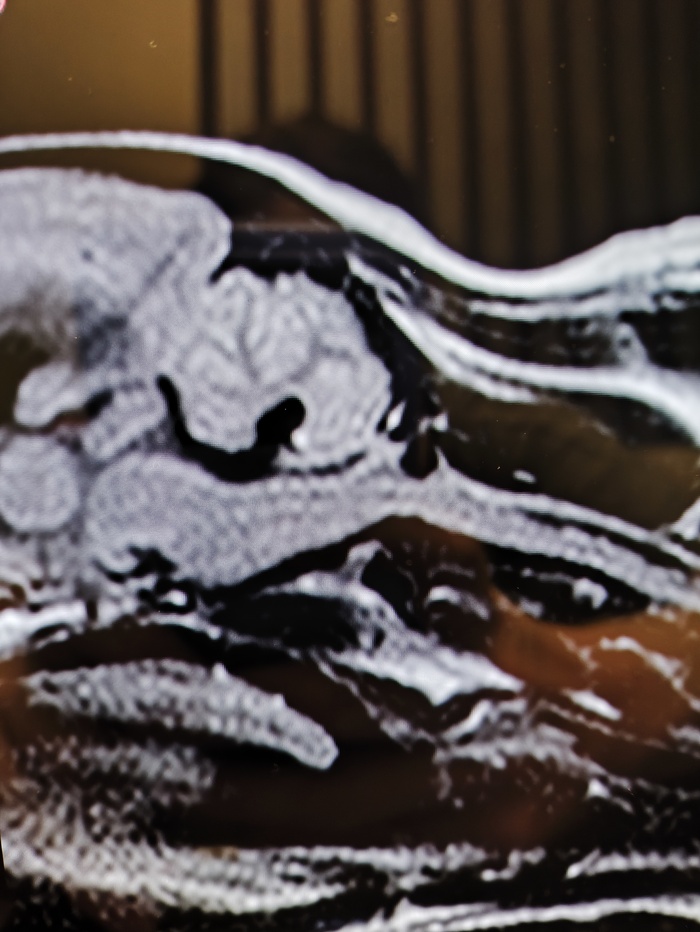

Киари синдром у собаки, сирингомиелия. Нужен совет

Всем привет. Есть собака (шпиц 3года, 3 кг). У него подозревают Киари-синдром, сирингомиелию. Сделали ему мрт.

В шейном отделе признаки дегенеративно-дистрофических изменений межпозвонковых дисков. Признаки сирингомиелии, отека спинного мозга по типу пресирингса на уровне сегмента С5-С7.

Голова: признаки краниоцервикальной мальформации, признаки вентрикуломегалии, признаки частично-пустого турецкого седла.

Очень интересно, нормальное ли положение мозжечка или нет. Виден ли Киари синдром или нет?

На следующей неделе я веду его на прием, но ветеринар уже говорил про операцию.